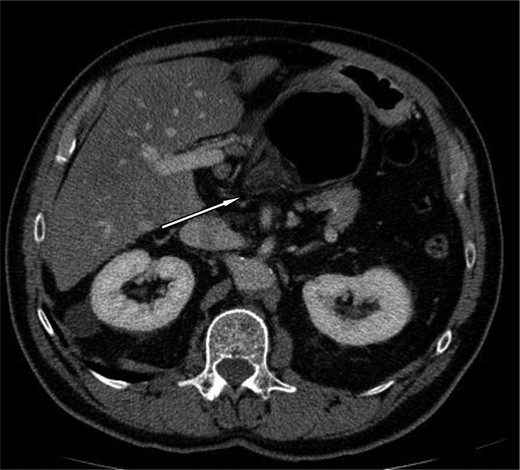

A 69-year-old patient presented to our emergency room with progressive dull abdominal pain and distension without nausea, vomiting or change in bowel habits. Physical examination showed pain with moderate guarding in the right upper and lower quadrants. A plain abdominal X-ray and a CT scan were performed. Radiological findings suggested the diagnosis of an internal hernia through the epiploic foramen and containing the right colon with important distension of the caecum (Fig. 1). Surgical exploration was then performed using an open approach. At laparotomy, we found an internal herniation of the caecum and the entire ascending colon through the foramen of Winslow (Figs 2 and 3). After hernia reduction, multiple patchy areas of caecal necrosis were observed (Fig. 4). A formal right hemi-colectomy was therefore performed. The postoperative recovery was uneventful.

The herniated segment after reduction, with areas of necrosis.